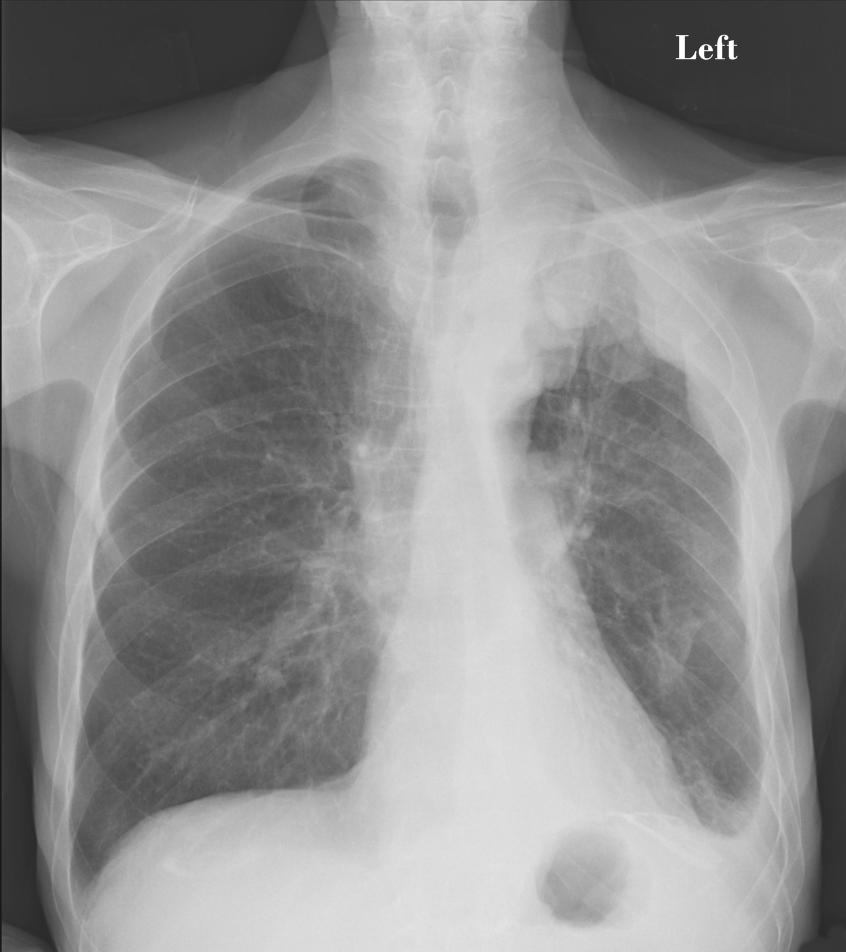

Katherine opted for the most aggressive and riskiest treatment option, but also the one most likely to cure her cancer. As optimistic as ever, Katherine underwent an extrapleural pneumonectomy. Her surgeon removed the tissue called the pleura, in which the cancer originated, her entire right lung, and part of her diaphragm. She followed up this major and risky surgery with months of radiation treatment to try to kill every last cancer cell.

After several months of treatment and recovery from treatment—and adjusting to life with just one lung—Katherine returned to her doctors for regular checkups. After a few months, then six months, and finally a year, Katherine still had no signs of cancer in her. She had achieved remission—an accomplishment that is so rare for anyone with mesothelioma.